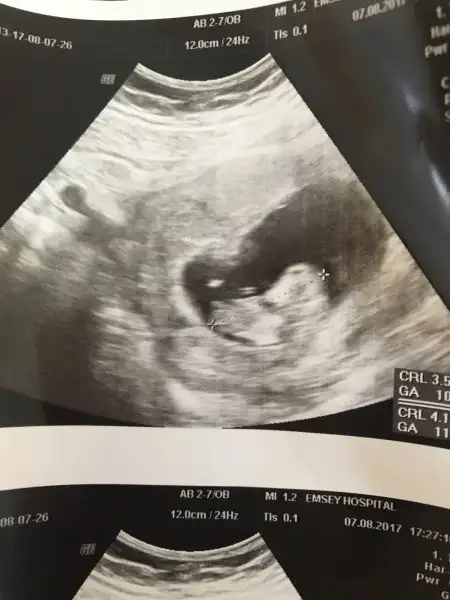

Umudunu kesme cnm dua etSağol canım kafa 2 hafta önde gidiyor vücut iki hafta geri ellerinin bilek bölümünde kalbinde beyninde daha bilmiyorum iki ayrı doktor da bunlara benzer şeyler söyledi allahtan umut kesilmezmiş ama umudum yok